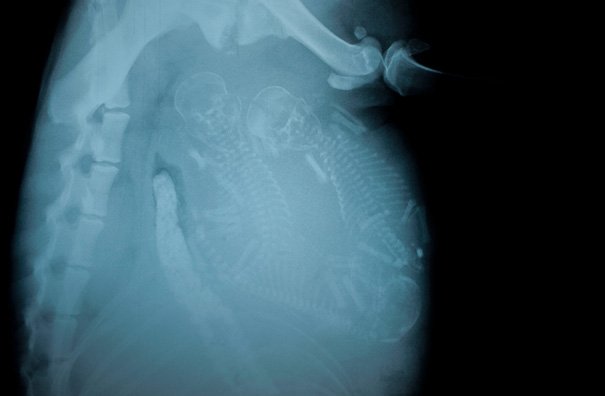

Итак, как выглядят рентгеновские снимки беременных животных:

морская свинка